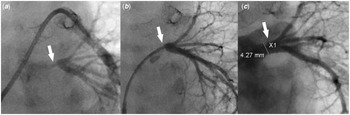

Figure 3. (a) Pulmonary artery wedge angiogram shows severe left common pulmonary vein ostial stenosis (white arrow). ( b) Left common pulmonary vein angiogram shows severe left common pulmonary vein stenosis (white arrow) with well-developed distal pulmonary vein branches. ( c) Left pulmonary vein angiogram post-stent placement shows a well-positioned stent (white arrow) inside the left common pulmonary vein with good expansion, resolution of the stenosis, and no evidence of vascular injury or jailing of the segmental left pulmonary veins.

A 3-month-old male weighing 4.8 kg was born with truncus arteriosus, interrupted aortic arch, and persistent left superior caval vein draining into the right atrium via what was initially thought to be fully roofed coronary sinus. He underwent surgical repair on day 10 of life consisting of end-end arch repair, ventricle septal defect closure, and placement of right ventricle-pulmonary artery homograft. Immediately after repair, stents were placed in the proximal right and left pulmonary arteries due to severe stenosis. Due to the persistent low oxygen saturation (in the mid-80s), a bubble study echocardiogram was performed which revealed that the coronary sinus was partially unroofed. A cardiac CT scan 3 weeks post-repair showed stenosis of the left pulmonary artery proximal to the stent, as well as normal size common right and common left pulmonary veins. An echocardiogram at 3 months of age revealed increased estimated right ventricle systolic pressure, increased flow velocity in the branch pulmonary arteries, flow turbulence in the common left pulmonary vein, no atrial septal defect, dilated coronary sinus ostium, and unroofed distal coronary sinus with the unroofed segment measuring 7 mm in length (Figs 1 and 2). He was taken to the cardiac catheterisation lab for possible intervention on the stented pulmonary arteries. The right femoral vein and artery were accessed using a 5-Fr sheath and a 20-gauge catheter, respectively. Haemodynamic measurements showed elevated distal pulmonary artery pressure with a mean of 26 mmHg and an elevated calculated pulmonary vascular resistance (9.8 Wood units × m2). Balloon angioplasty was then performed in the right and left pulmonary artery stents, along with the placement of an additional stent in the proximal left pulmonary artery to treat the aforementioned stenosis. The left pulmonary artery wedge angiogram showed severe ostial stenosis of the common left pulmonary vein (Fig 3A). Attempts to cross the atrial septum (probing the foramen ovale) were unsuccessful. Knowing the patient had an unroofed coronary sinus, we elected to attempt left atrial access via the coronary sinus. A coaxial system consisting of a 5-Fr JR4 guide catheter (Medtronic), 4-Fr JR 2 catheter (Cook Medical), and 0.035" angled glide wire (Terumo) was inserted through the right femoral vein sheath into the coronary sinus. The catheters were oriented superiorly and rightward. The wire was advanced to cross the coronary sinus into the left atrium. The catheters were then advanced over the wire inside the left atrium. The angled glide wire was exchanged for a 0.014" Choice wire (Boston Scientific). The catheters were turned toward the common left pulmonary vein. The Choice wire was manipulated to cannulate the common left pulmonary vein. The JR2 catheter was then advanced over the wire into the left lower pulmonary vein (Fig 2). Pressure measurements revealed a gradient of 16 mmHg across the stenosis. Angiograms showed severe stenosis of the left pulmonary vein just distal to the ostium and the normal pulmonary vein measuring 4.2 mm (Fig 3B). The Choice wire was exchanged for a stiffer coronary wire [0.014" Asahi Grand Slam wire (Abbott)] to provide more support for pulmonary vein stent placement. Then, the 5-Fr guide catheter was advanced over the JR2 catheter inside the vein and the JR2 catheter was removed. A 4 × 8 mm Synergy everolimus-eluting stent (Boston Scientific) was advanced over the wire inside the guide catheter and centred across the stenotic portion. The stent was deployed by inflating the balloon to 18 atmospheres (the rated burst pressure) to achieve a stent diameter slightly larger than 4 mm to match the normal distal pulmonary vein segment. Angiography revealed a well-positioned stent (Fig 3C). Pressure measurement showed no gradient across the stent. No significant improvement in his oxygen saturation was noticed at the end of the procedure. The patient was discharged home on the same home dose of aspirin and started on Sildenafil. Over the next few weeks following the procedure, his oxygen saturation has increased to 93–95%.